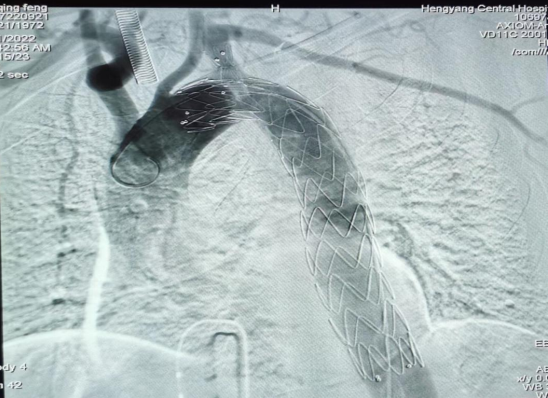

疾病的兇險(xiǎn)與手術(shù)費(fèi)的昂貴,讓許先生一家人左右為難。了解許先生經(jīng)濟(jì)困難,心血管中心趙慶禧主任醫(yī)師與患者充分溝通后,決定放棄傳統(tǒng)的穿刺方法(需使用血管縫合器),行股動脈和左側(cè)肱動脈切開入路,既保證了手術(shù)安全性又兼顧了經(jīng)濟(jì)性。最終在9月21日,許先生愿意接受介入微創(chuàng)治療。趙慶禧帶領(lǐng)介入團(tuán)隊(duì)和麻醉科團(tuán)隊(duì)密切配合,為其施行全麻下行“Castor分類型覆膜支架植入術(shù)”。僅在患者的左肱動脈,右股總動脈處分別做不到1cm的小切口,然后在DSA引導(dǎo)下精確定位,釋放覆膜支架一枚,保住鎖骨下動脈的同時(shí)也堵住了主動脈內(nèi)膜破口,手術(shù)歷時(shí)三個(gè)小時(shí),順利完成,“致命炸彈”被徹底拆除,術(shù)后許先生恢復(fù)良好,于住院的第30天順利出院。

(術(shù)中釋放的一體式覆膜支架)